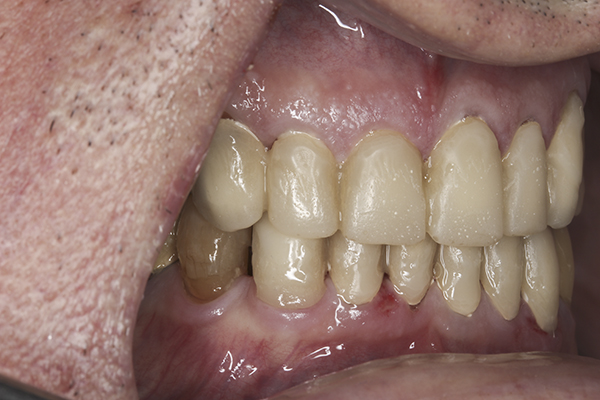

(9.) Preoperative right lateral, closed view.

Figure 9

(10.) Preoperative anterior, closed view. Note the end-to-end occlusion of the anterior teeth and the wear on the incisors and centrals resulting in no anterior or canine guidance.

Figure 10

(11.) Preoperative left lateral, closed view.

Figure 11